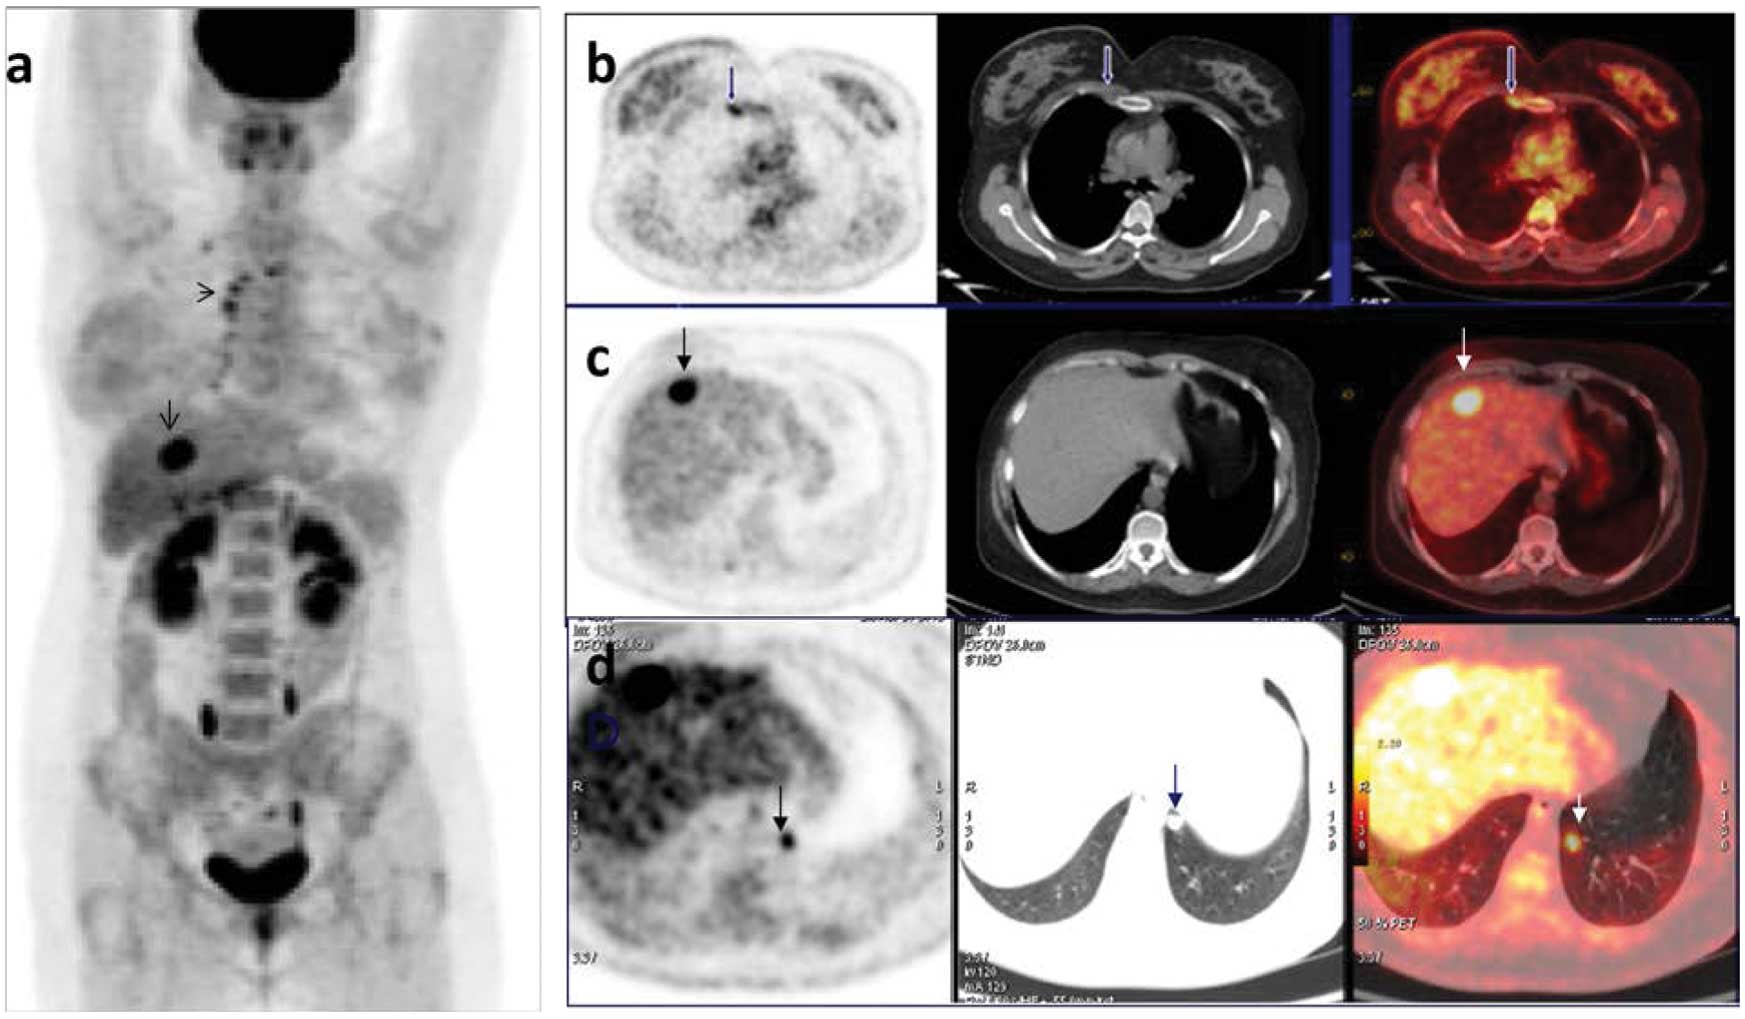

Panel Of 18 F FDG PET CT Imaging At 6 Months Follow up Of Patient 7

https://www.researchgate.net/profile/Brunolf_Lagerveld/publication/286478657/figure/download/fig6/AS:306456508289029@1450076333191/Panel-of-18-F-FDG-PET-CT-imaging-at-6-months-follow-up-of-patient-7-There-are-2-FDG-avid.png